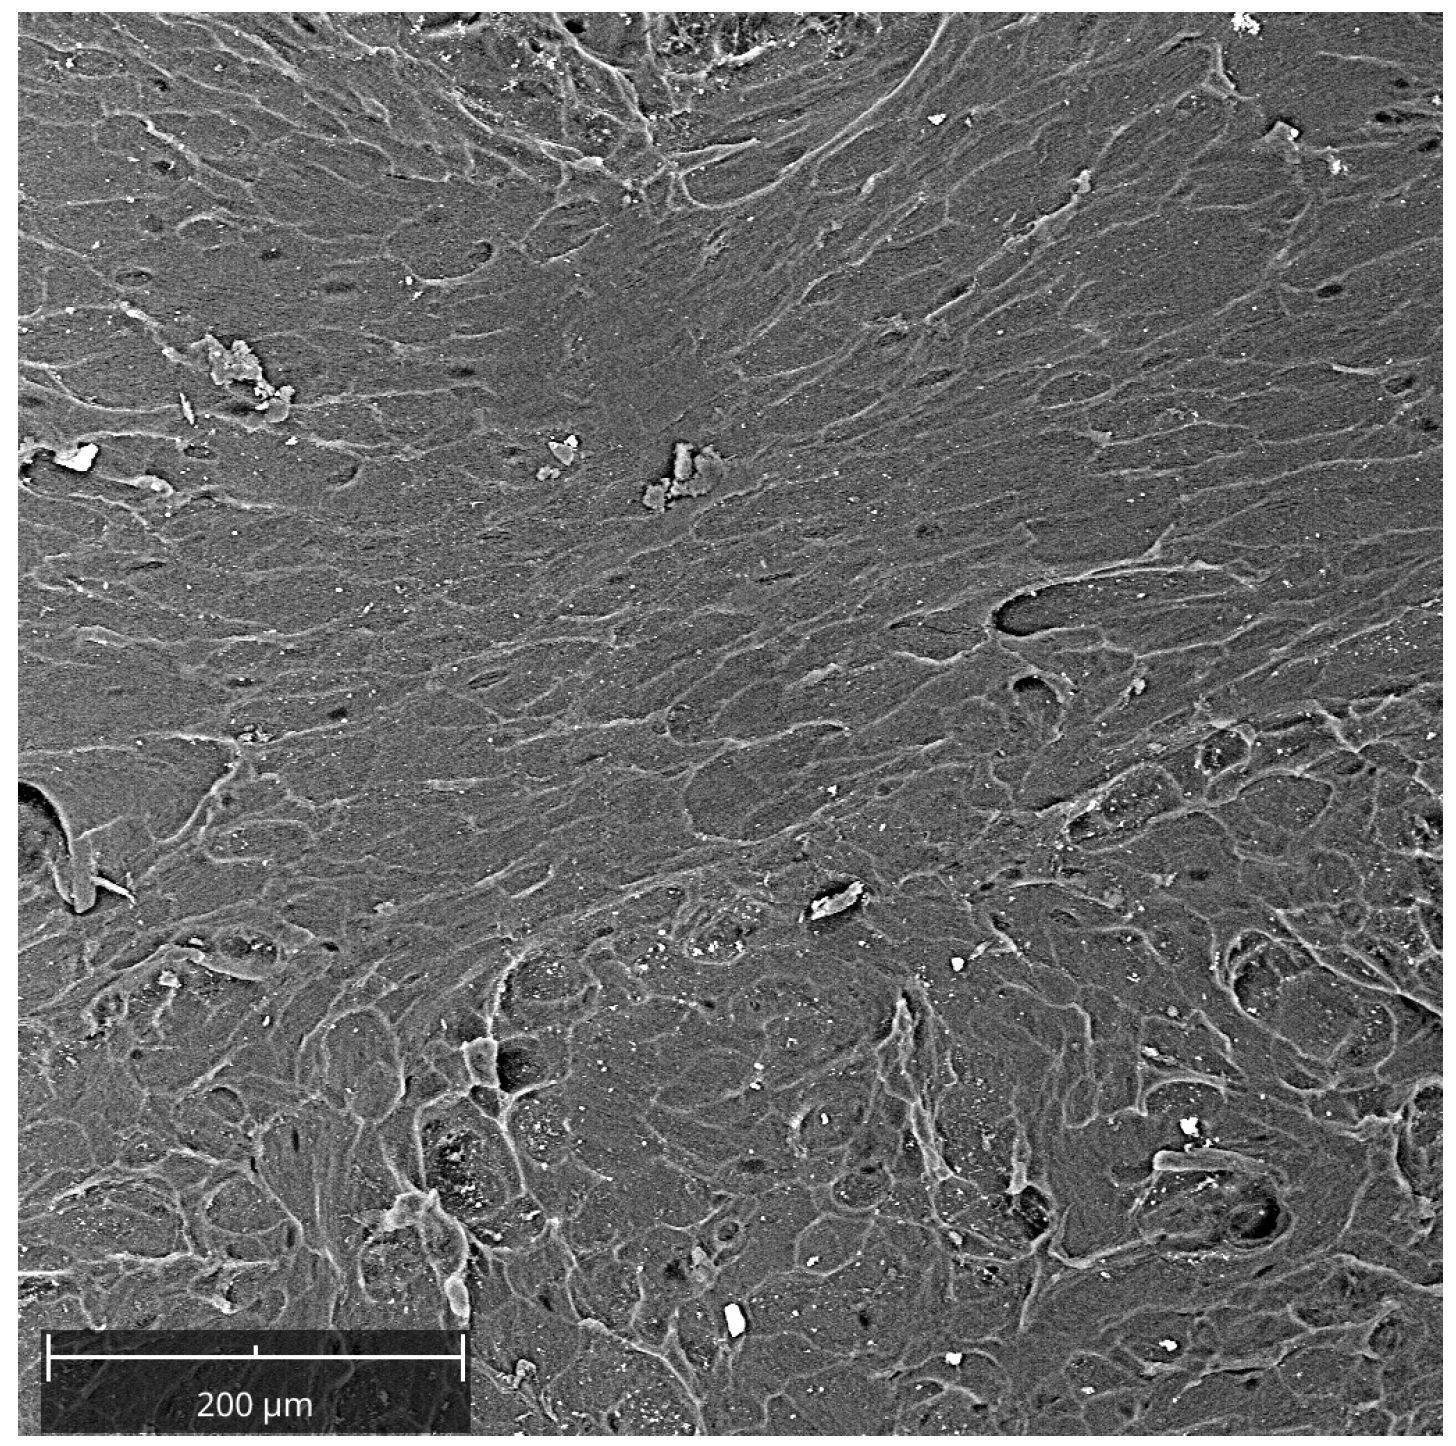

- In TEST 1, the response of human oral osteoblasts (HOBs) was evaluated for lamina compared to ones seeded on a well/plate. Two groups were compared, HOBs seeded on the plate as control (CTRL) and HOBs seeded on the membrane (lamina). SEM analyses were performed to study the topographical characteristics of the membrane surface and the adhesion and morphology of cells at 3 days. The viability was assessed at 3 days by MTT assay, the ALP activity was investigated at 7 days by ALP enzymatic assay, and calcium deposition at 14 days was assessed by Alizarin Red staining and by the measurement of absorbance;

2.3. Characterization of the Lamina

3.1. Characterization of the Lamina